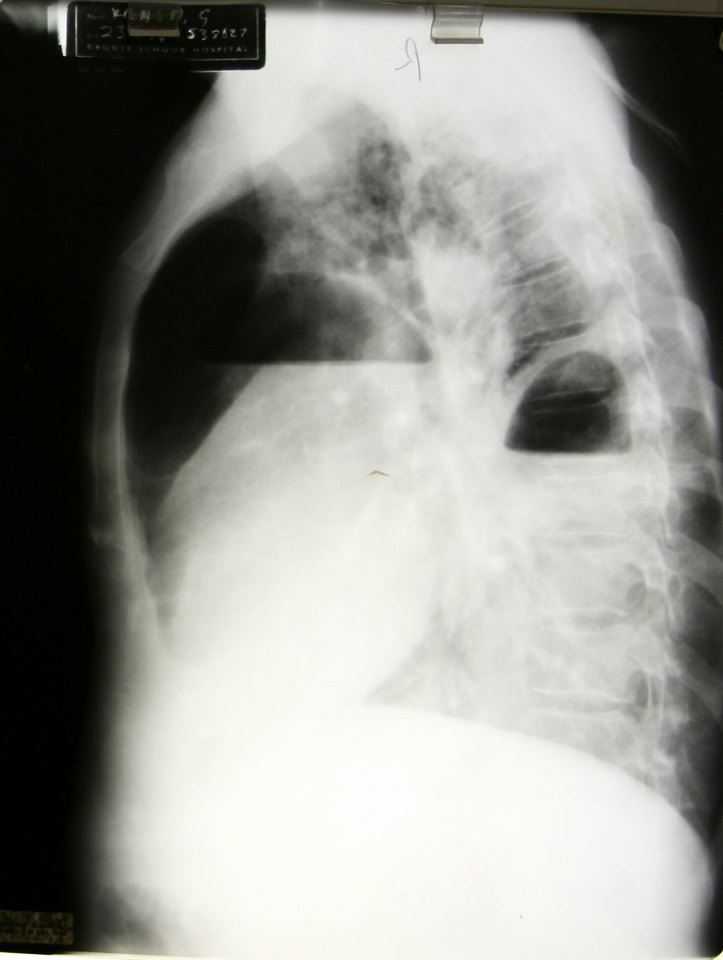

This patient has both a pulmonary abscess and an empyema at the same time! |

Lateral view, same patient |